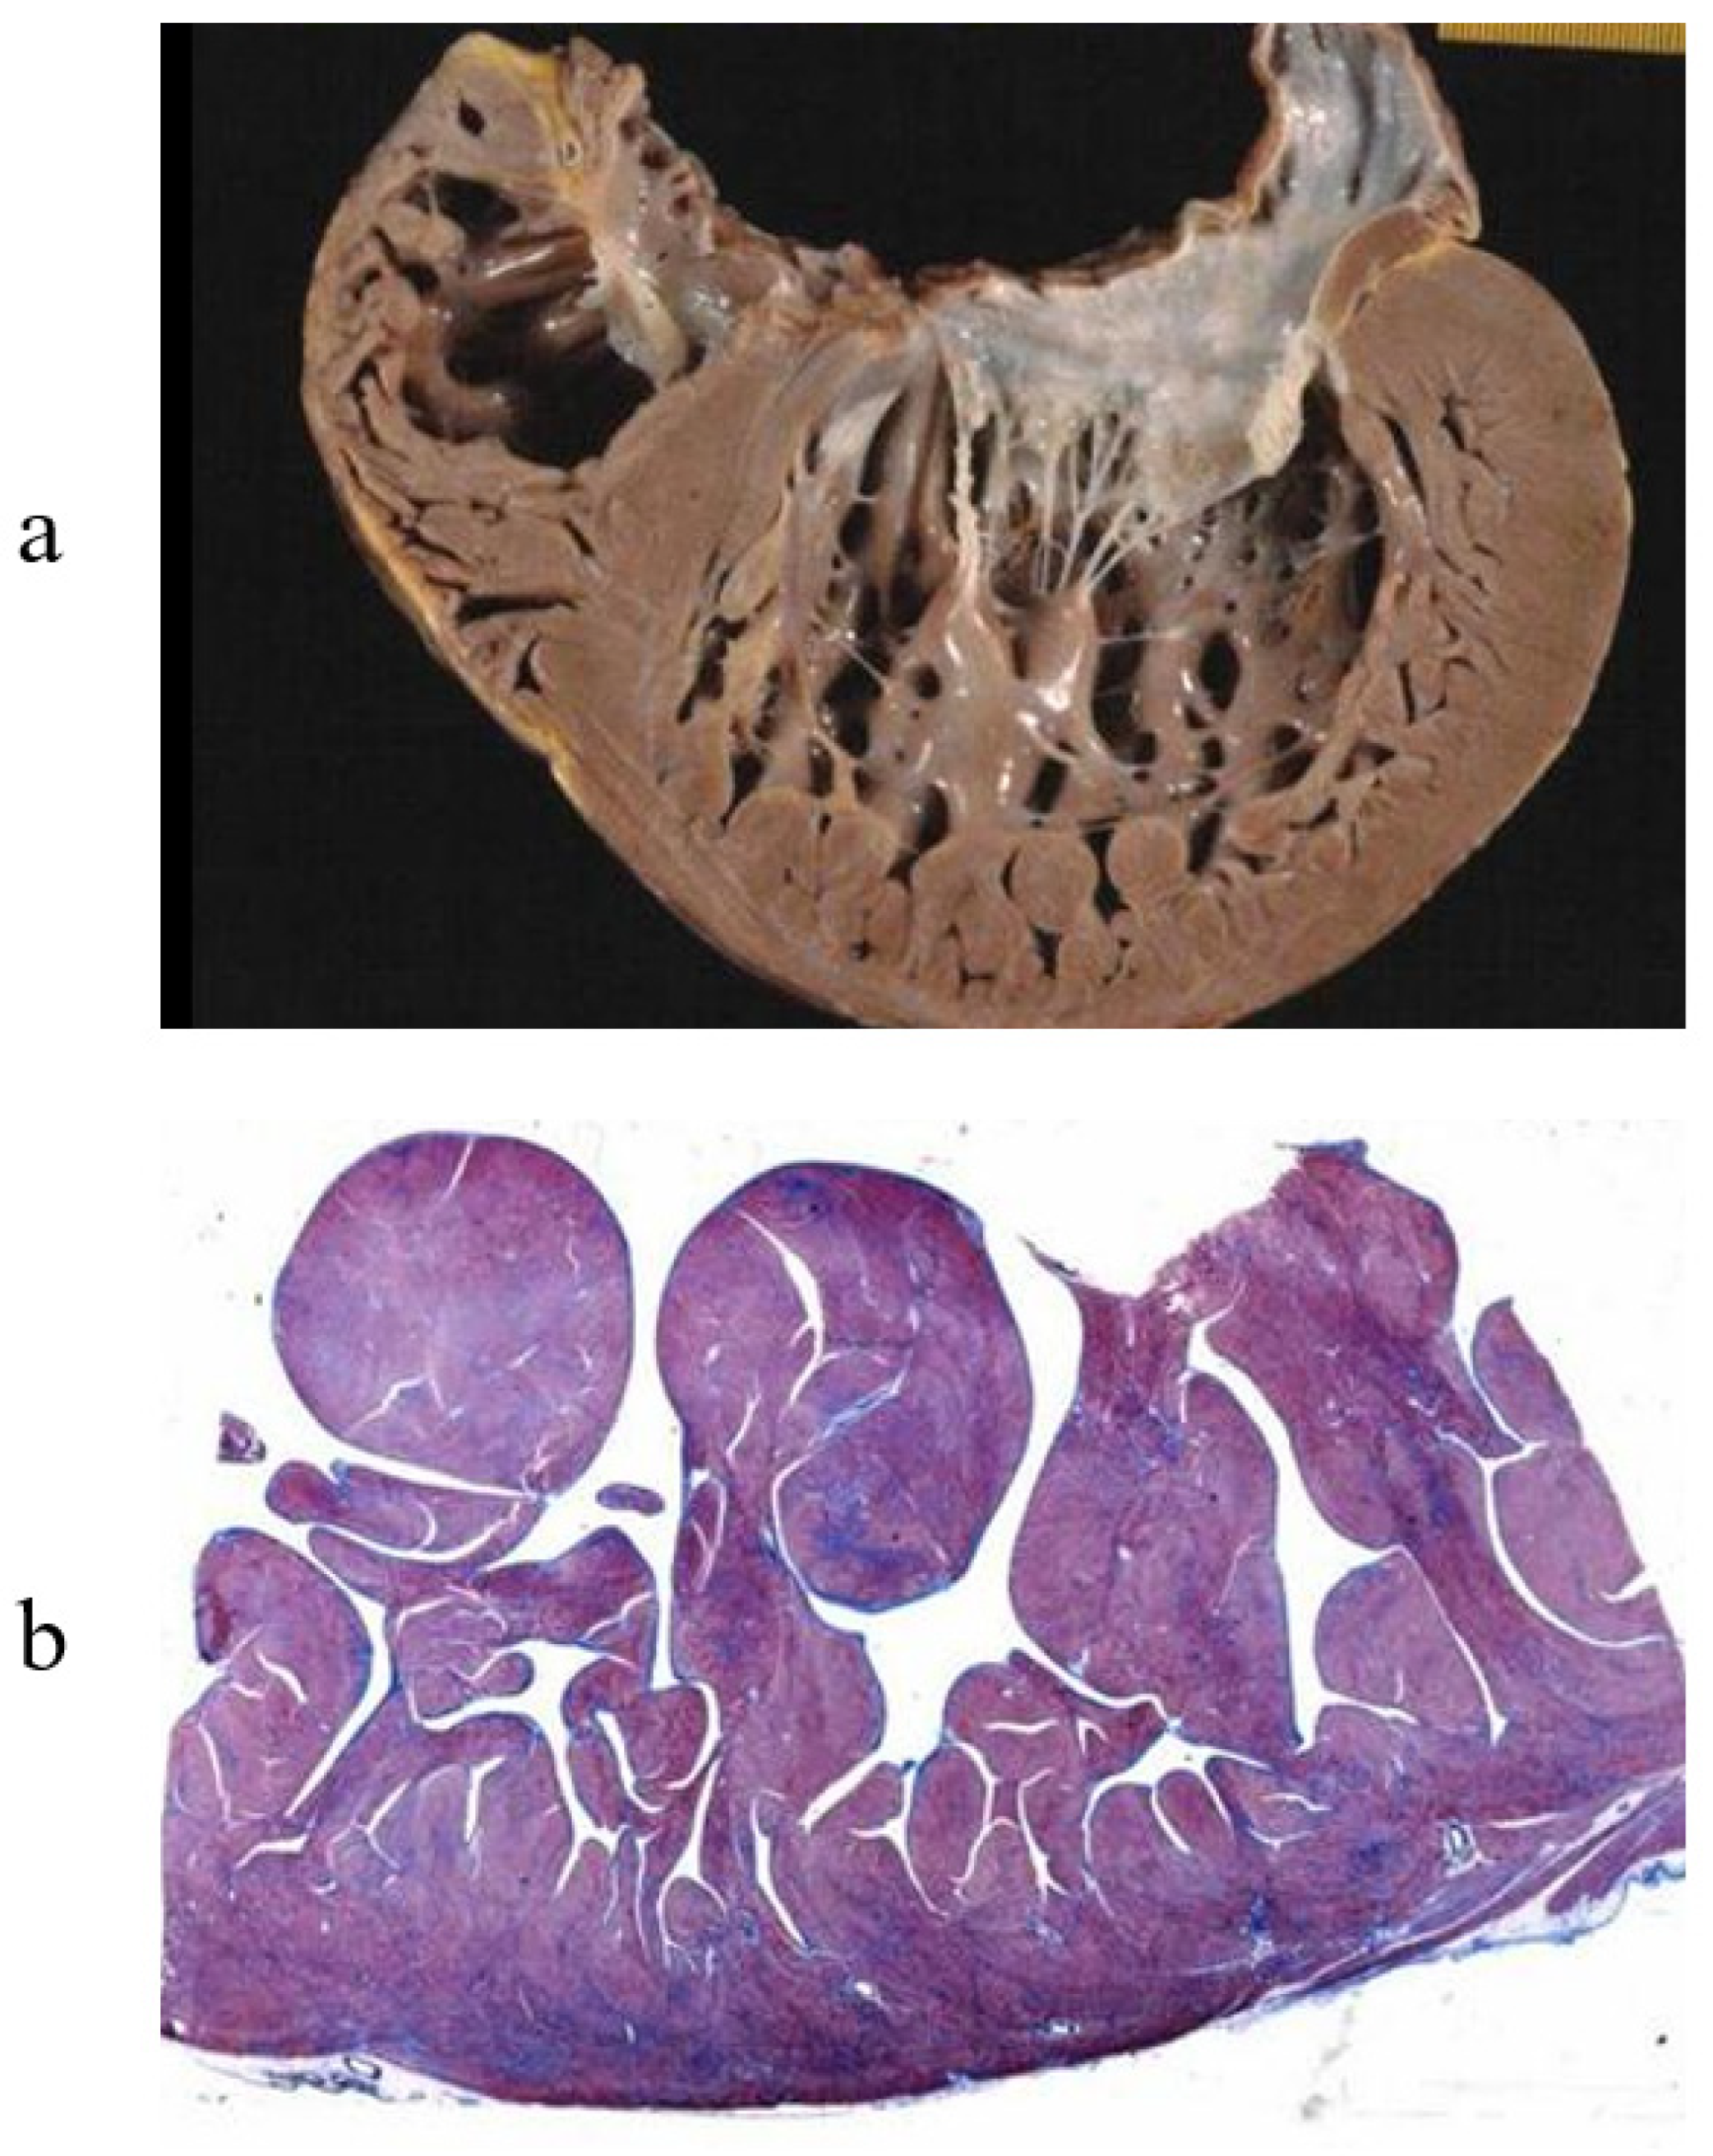

3. Arrhythmogenic Cardiomyopathy

7. Clinical Indications of Endomyocardial Biopsy